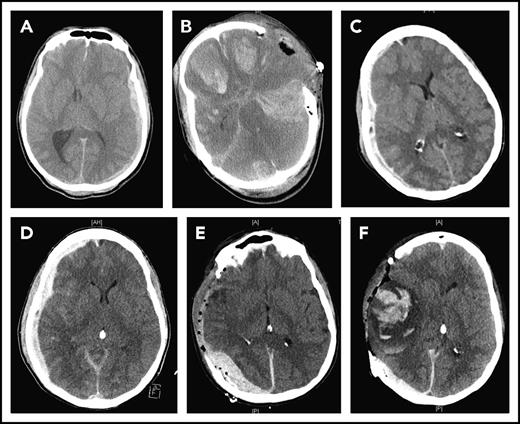

TBI-induced coagulopathy manifests as disseminated intracranial hemorrhage (Figure 1A), delayed intracranial or intracerebral hematoma (Figure 1B), and systemic bleeding.10-12 It occurs early, often in a prehospital setting, and is closely associated with poor clinical outcomes.8,10,13 The international normalized ratio (INR) and thromboelastogram are laboratory assays that are widely used to diagnose TBI-induced coagulopathy. However, both INR and thromboelastogram are limited in predicting coagulopathy before it develops. New biomarkers and laboratory tests are therefore needed to timely, accurately, and reliably predict the development and severity of TBI-induced coagulopathy so that preventive measures and targeted therapeutics can be developed.

CT images of 2 TBI patients. The first patient suffered from subdural hematoma after a step fall (A) and developed diffused cerebral bleeding immediately after decompressive craniectomy (B). The second patient suffered from progressive subdural hematoma after a car accident (C-D) and developed delayed subdural and intracerebral hematomas after decompressive cranioctomy (E-F).

The BBB disruption allows the vascular leakage of fluid to cause cerebral edema and releases brain-derived substances into the circulation to trigger systemic coagulopathy. Because the systemic dissemination of brain-derived molecules requires sufficient cerebral blood flow, one may ask whether high intracranial pressure, which suppresses the cerebral circulation, could slow the systemic release of brain-derived procoagulant substances, such as cellular MVs.30,31 If this is proven to be the case, decompressive craniectomy or other means of reducing intracranial pressure may inadvertently promote the systemic release of the brain-derived molecules by restoring the cerebral blood flow, following a similar course of ischemic reperfusion injury. In this case, the prophylactic use of MV-scavenging factors, such as lactadherin,32 before surgery may prevent the postoperational development of disseminated intracranial hemorrhage or delayed intracranial or intracerebral hematoma after surgery (Figure 1).